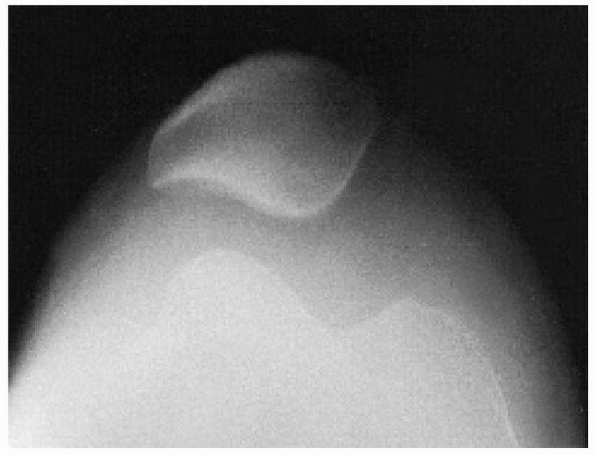

should begin with anteroposterior, lateral, and skyline plain

radiographs. However, a roentgenographic diagnosis can be difficult

because even a large osteochondral fragment may contain only a small

ossified portion that is visible on plain radiographs. A tunnel view

may help locate a fragment in the region of the intercondylar notch.

Because the osteochondral fragment may be difficult to see on plain

radiographs, radiographs must be carefully assessed for even the

smallest ossified fragment (Fig. 24-15).

![]() |

|

FIGURE 24-15 Osteochondral fracture of lateral femoral condyle after patellar dislocation. A. Fragment seen in lateral joint space. B. Lateral view.